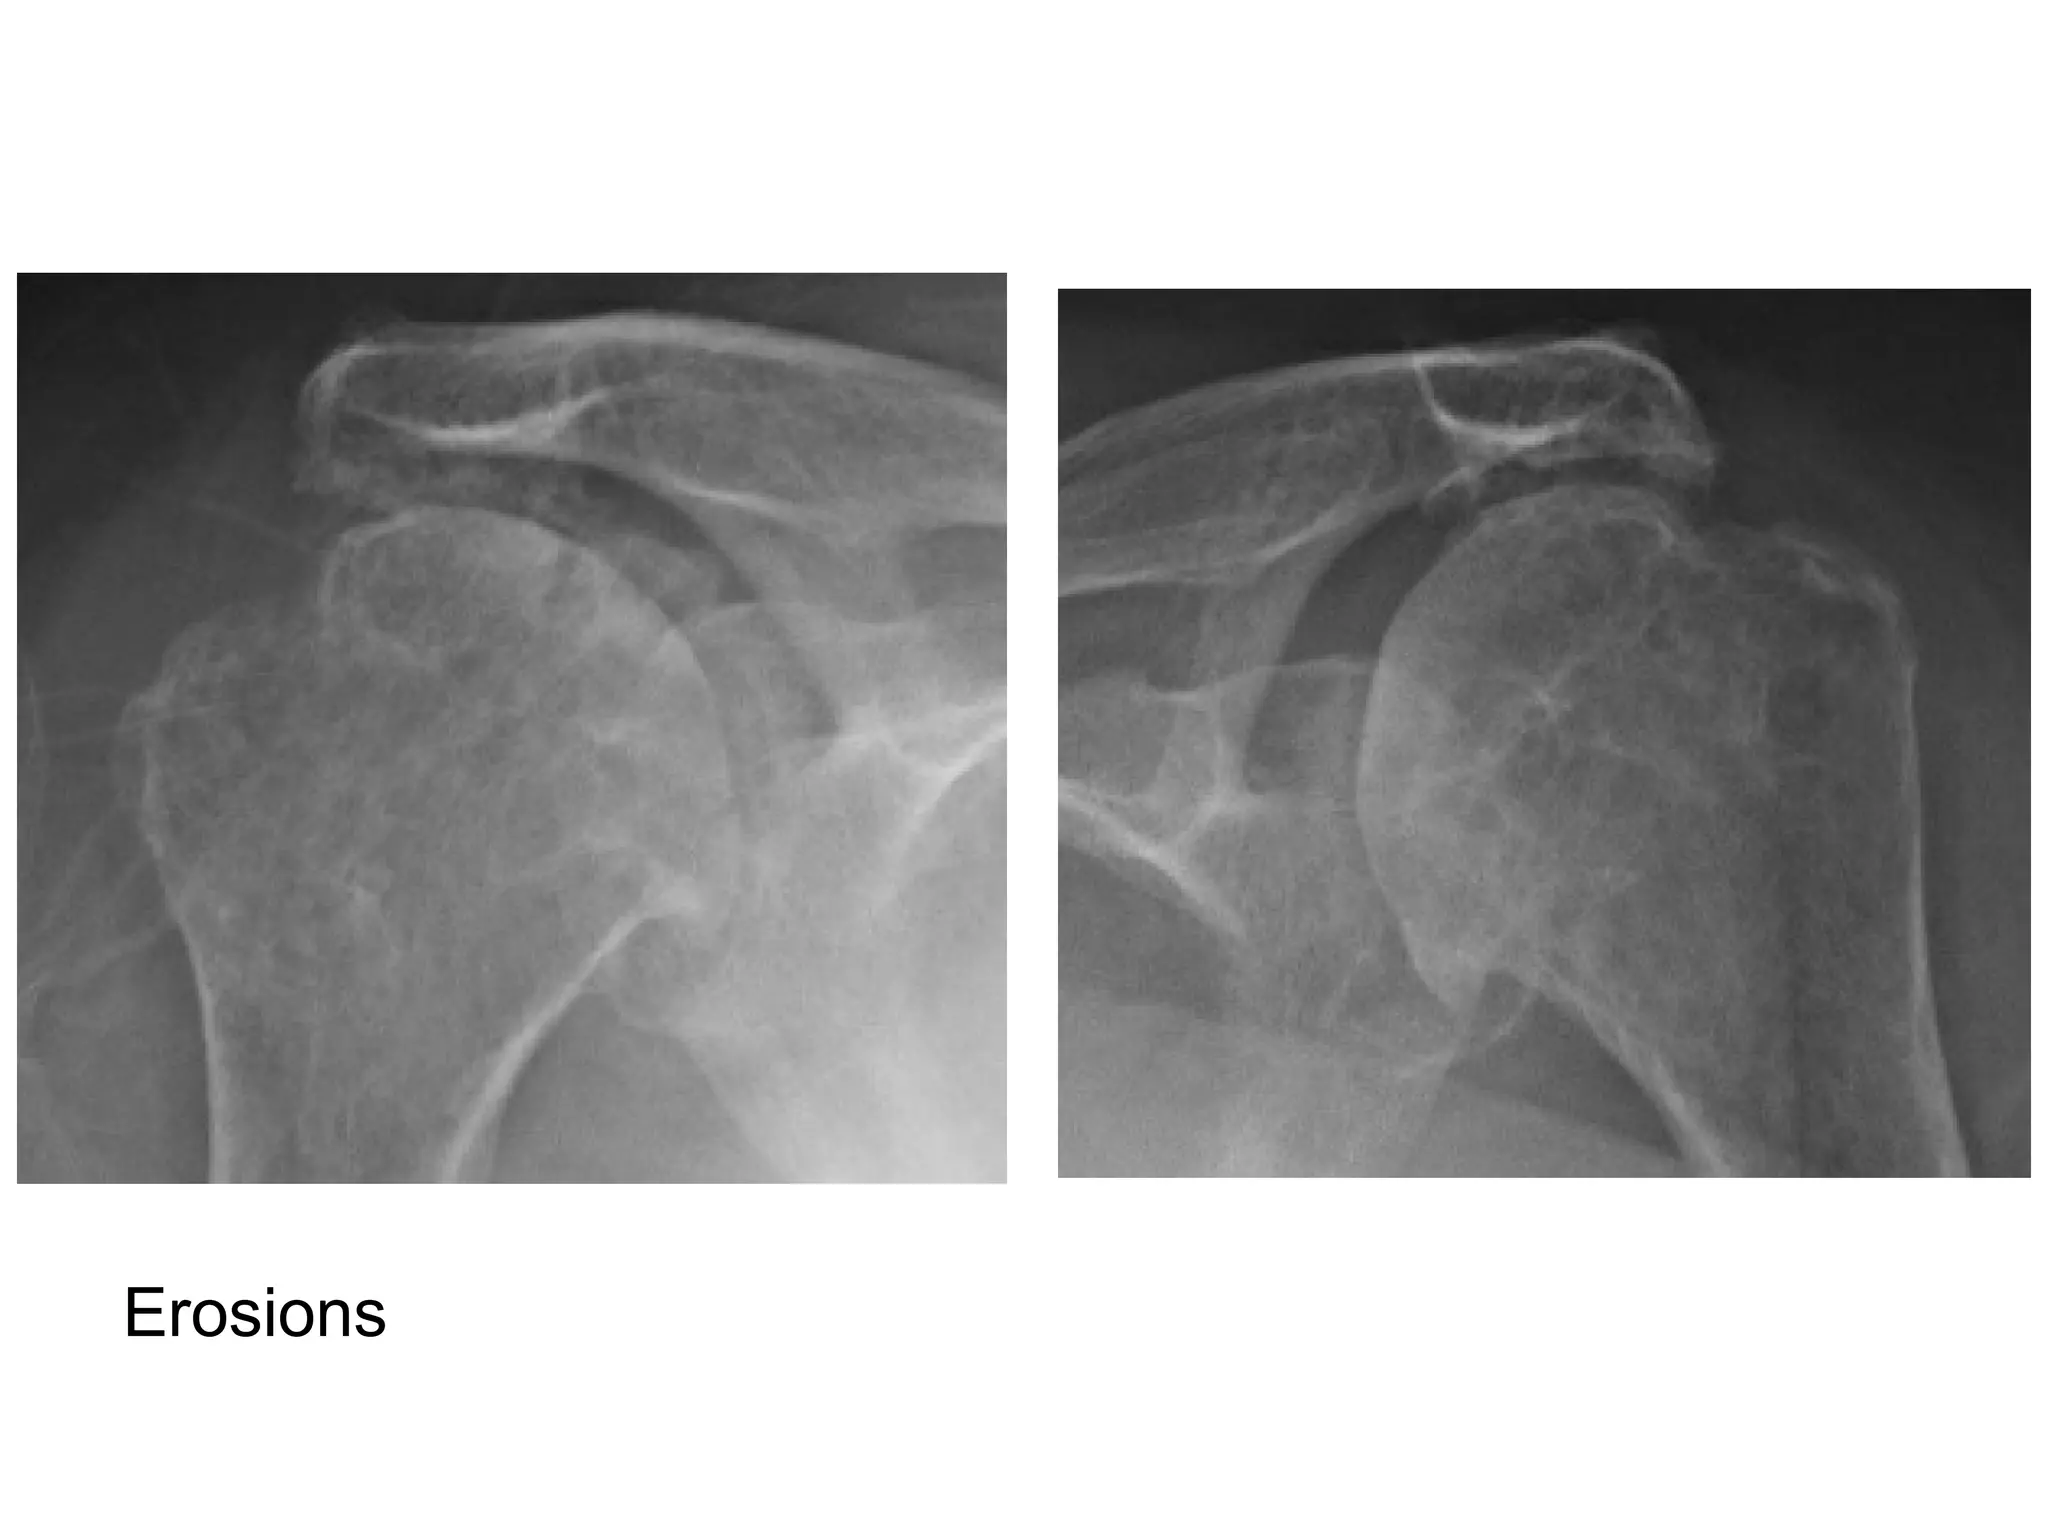

1-RA in shoulder :

-Erosion of the distal clavicle

-Marginal erosions of the humeral head , tends to

occur in the lateral aspect of the humeral heads

-Rotator cuff tear >> classic high riding humerus

Erosion of distal clavicle

Erosions